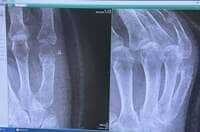

この日は「皆さん経過観察の結果 気になってらしたでしょう」と切り出し、医師から「おっ!!良いじゃないですかぁー」と言われたこと説明。「くっつき始めてる」と嬉しそうに述べ、レントゲン検査で撮影された手の写真を公開した。